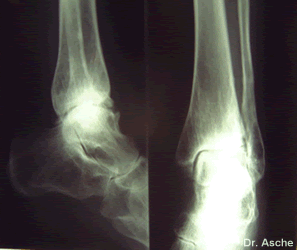

Nach drittgradiger Spruggelenksfraktur bekommt die Patientin nach 8 Jahren eine schwere schmerzhafte Arthrose. Orthopädische Schuhe bringen keine Linderung.